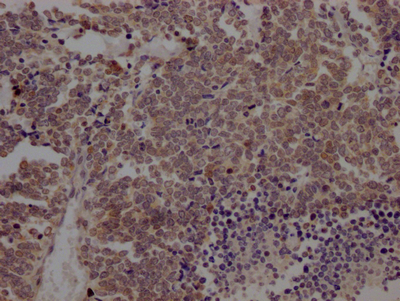

IHC image of CSB-RA916472A0HU diluted at 1:100 and staining in paraffin-embedded human liver cancer performed on a Leica BondTM system. After dewaxing and hydration, antigen retrieval was mediated by high pressure in a citrate buffer (pH 6.0). Section was blocked with 10% normal goat serum 30min at RT. Then primary antibody (1% BSA) was incubated at 4℃ overnight. The primary is detected by a Goat anti-rabbit IgG polymer labeled by HRP and visualized using 0.05% DAB.